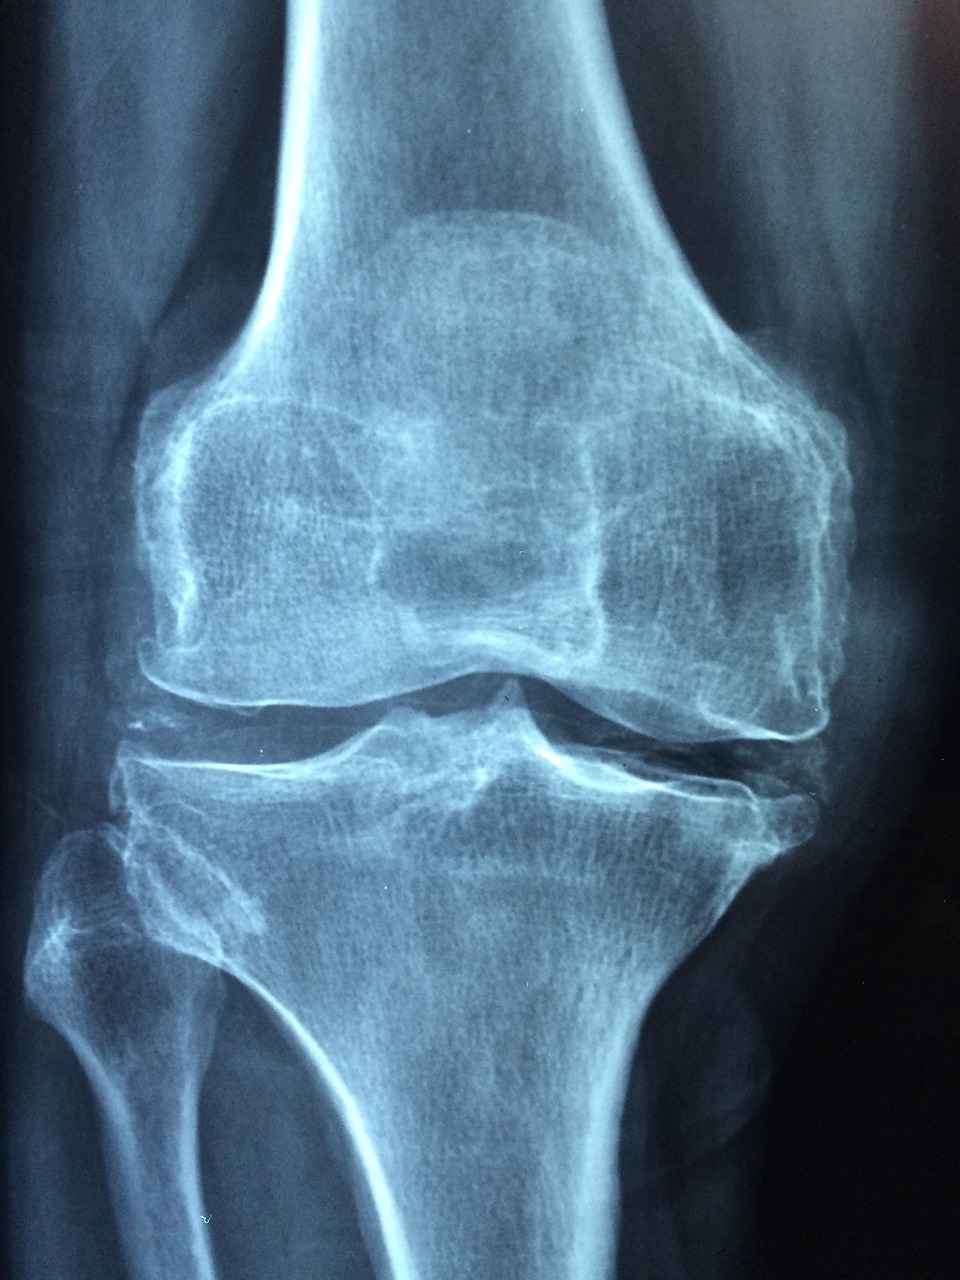

골다공증의 진단 방법

골다공증은 초기에 증상이 뚜렷하지 않기 때문에, 정기적인 검사와 평가가 중요합니다.

골다공증의 진단은 주로 뼈의 밀도를 측정하는 검사를 통해 이루어집니다.

뼈밀도 검사 (Bone Density Test)

이중 에너지 X선 흡수계측법 (DEXA 스캔): 가장 흔하게 사용되는 방법으로, 특히 척추와 고관절의 뼈 밀도를 측정합니다.

낮은 뼈 밀도는 골다공증의 위험을 나타냅니다.

Q: 골다공증으로 인한 골절은 어떻게 알 수 있나요?

A: 가벼운 넘어짐이나 충격으로도 골절이 발생하고, 골절 부위에서 심한 통증이 발생할 수 있습니다. 특히 고관절, 척추, 손목 골절이 흔합니다.